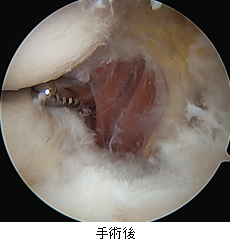

肩の痛みは外来で遭遇する頻度の高い症状です。多くは肩関節周囲炎(いわゆる四十肩・五十肩)によるものですが、一部には肩関節の周囲に存在する腱板という組織が損傷していることにより痛みが出ている場合があります(腱板断裂または損傷)。加齢性の変化で切れる場合や、外傷性の場合、また肩を使う仕事やスポーツなどにより摩耗して切れる場合があります。保存治療を行なっても痛みが続く場合、関節鏡を用いた腱板の修復術が行われます。

A: 腱板断裂部(上に見えているのが断端。下に上腕骨が見えている(黒丸部)。)

B: 断裂部を鉗子(右上)で牽引している。

C: 特殊な糸を用いて断裂部を上腕骨に縫着した(左側に青と白黒縞模様の糸による結び目が見えている)。